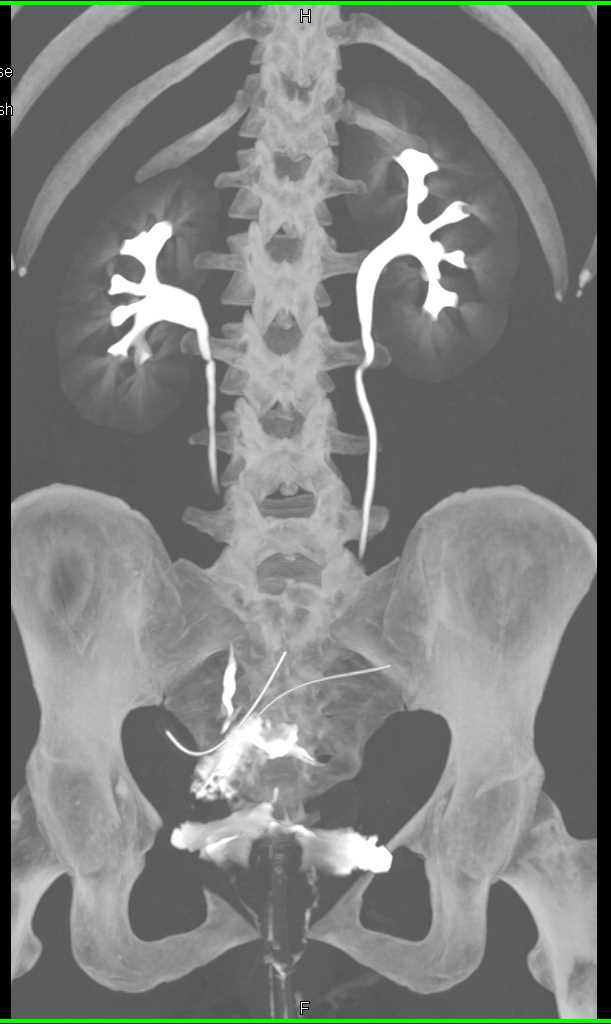

Urachal Carcinoma of the Bladder